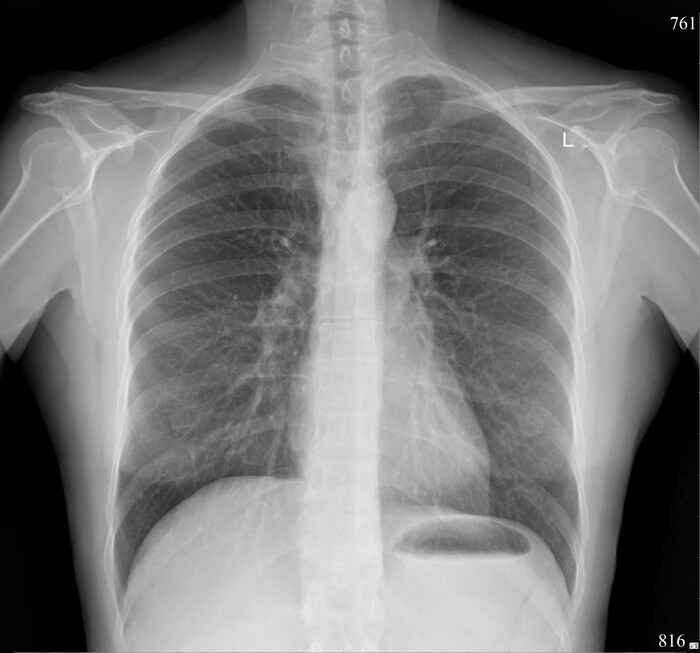

Ну и бонусом - как выглядят "нормальные" лёгкие.

Норма на рентгенограмме ОГК